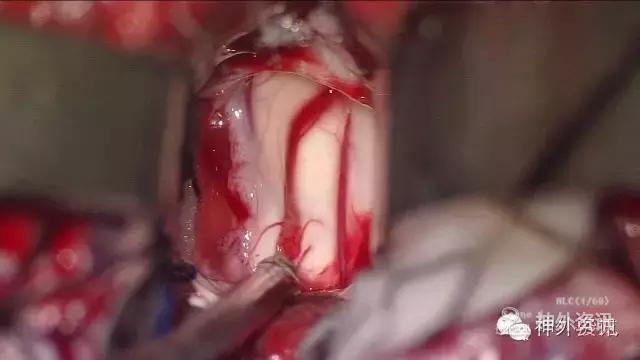

MRI:右侧丘脑占位,考虑胶质瘤可能性大(Ⅲ-Ⅳ级),病灶累及中脑右侧大脑脚,轻度脑积水;不除外转移瘤可能,请结合相关病史及检查。

初步诊断:丘脑占位,胶质瘤可能。

影像学检查: